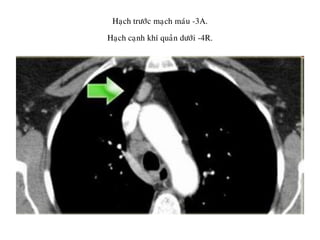

Haïch tröôùc maïch maùu -3A.

Haïch caïnh khí quaûn döôùi -4R.

4. HAÏCH CAÏNH KHÍ QUAÛN DÖÔÙI

Naèm döôùi ñöôøng ngang veõ tieáp tuyeán bôø treân

cung ñoäng maïch chuû.

4R-Haïch naèm beân (P) ñöôøng giöõa khí quaûn.

4L-Haïch naèm beân (T) ñöôøng giöõa khí quaûn môû roäng ñeán pheá quaûn